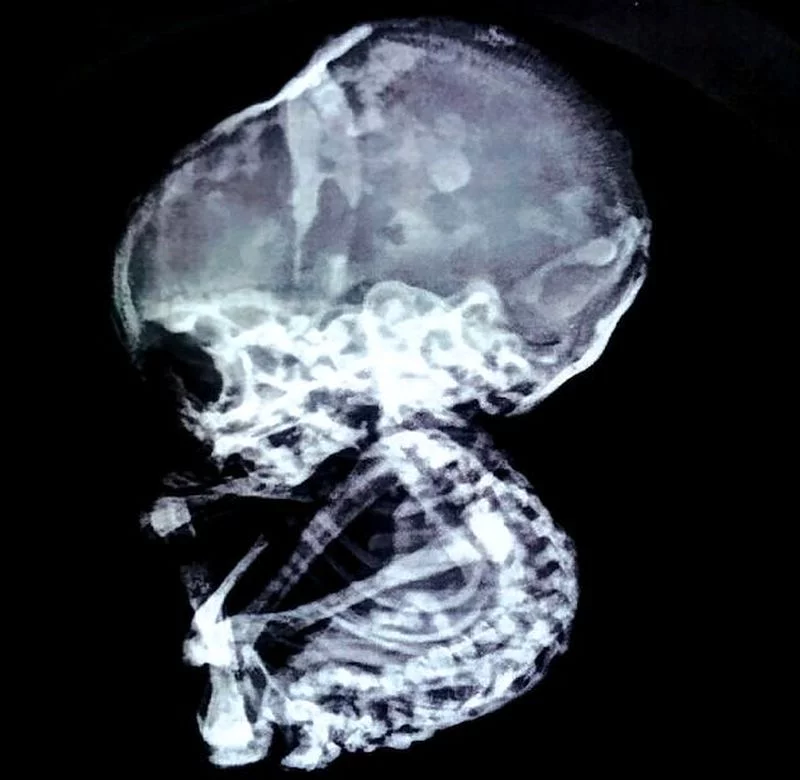

Dopiero wizyta u specjalisty od chirurgii laparoskopowej, doktora Nilesha Junankara, przyniosła odpowiedź na jej problemy. Dokładne badania wykazały, że niedrożność jelit kobiety spowodowana jest przez nietypową kamienną blokadę. Okazało się, że jest to skamieniały czteromiesięczny płód, którego nie usunięto całkowicie przed 15 laty. Po trwającej dwie godziny operacji usunięcia zatoru, kobieta wreszcie mogła odczuć ulgę.

Jak podkreślają indyjskie media, ciąża brzuszna to nie tak rzadka przypadłość. Łożysko może wrosnąć w ścianę jamy brzusznej nawet raz na 11 tysięcy ciąż. Wyjątkowo rzadko spotykanym zjawiskiem jest natomiast zwapnienie płodu czyli lithopedion, które w ciągu ostatnich kilkuset lat zostało stwierdzone zaledwie 300 razy. Dochodzi do niego w sytuacji, kiedy ciało kobiety nie umie samo wydalić martwego płodu.